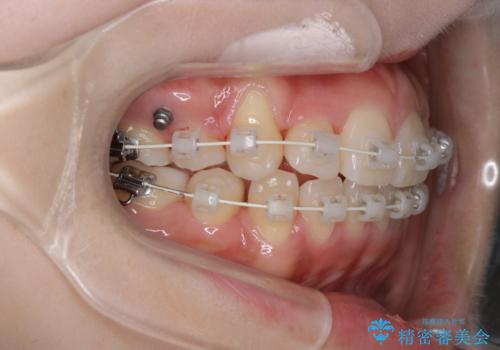

- 4番の歯を4本抜歯をし、上顎にマイクロインプラントを2本埋入し、遠心移動を行いました。

主訴のオープンバイトは改善し、抜歯をしたことで前歯が下がり綺麗になりました。抜歯矯正でしたが1年2か月という短い期間で終了しました。